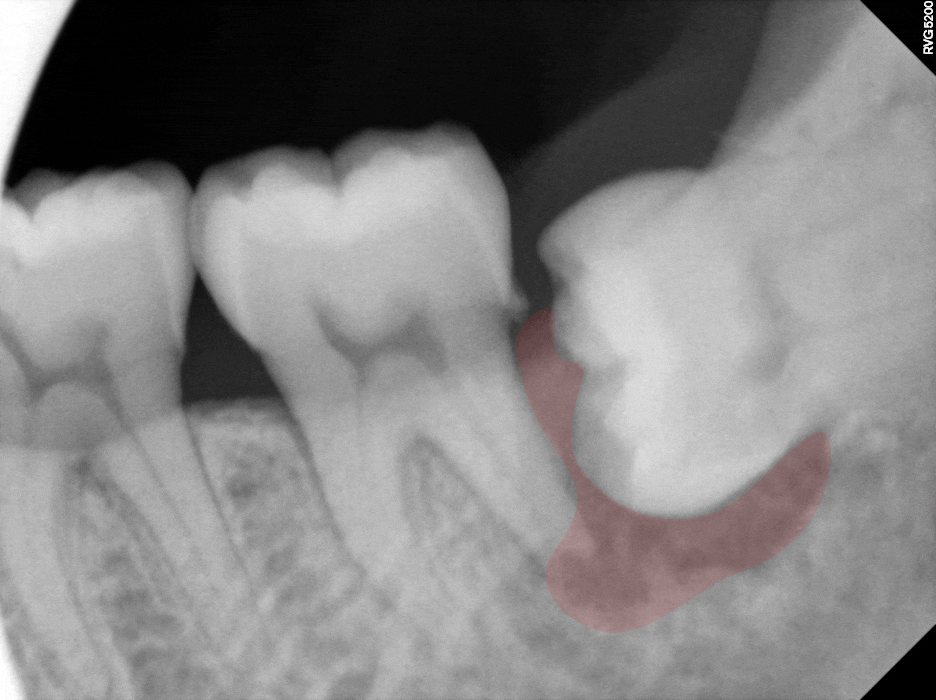

치아 곳곳에는 치석이 붙어 있고

치은 연하에도 치석이 부착된 것으로 봐서

치주염을 짐작해 볼 수 있는 환경이며,

실제로 CT 사진에서도

검게 보이는 영역이 관찰됩니다.

이는 방사선이 많이 통과되었다는 뜻으로

염증 반응 및 골소실을 의미합니다.

민락 치과 에서 확인한

제일 큰 문제는 염증의 범위입니다.

앞쪽 어금니에 확산된 모습으로,

원심 뿌리의 골소실이 큽니다.

이런 경우 큰 동요도는 물론이고

잇몸 치료로는 개선이 되지 않습니다.